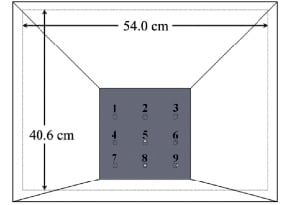

Another example of our current interests is the development of a multi-pinhole collimator (MPH) for use on one gamma-camera head of a general purpose SPECT system in combination with a fan-beam collimator on the second camera head for high resolution / sensitivity imaging of the striatal region of the brain in I-123 DaTscan imaging for Parkinson’s Disease. A rendering of the collimator is shown below followed by reconstructed simulated images of the strata for MPH, Fan, and Combined imaging. These investigations are funded by NIH grant R01-EB022092.

| Rendering of the MPH collimator showing the aperture plate with 9 pinholes. |